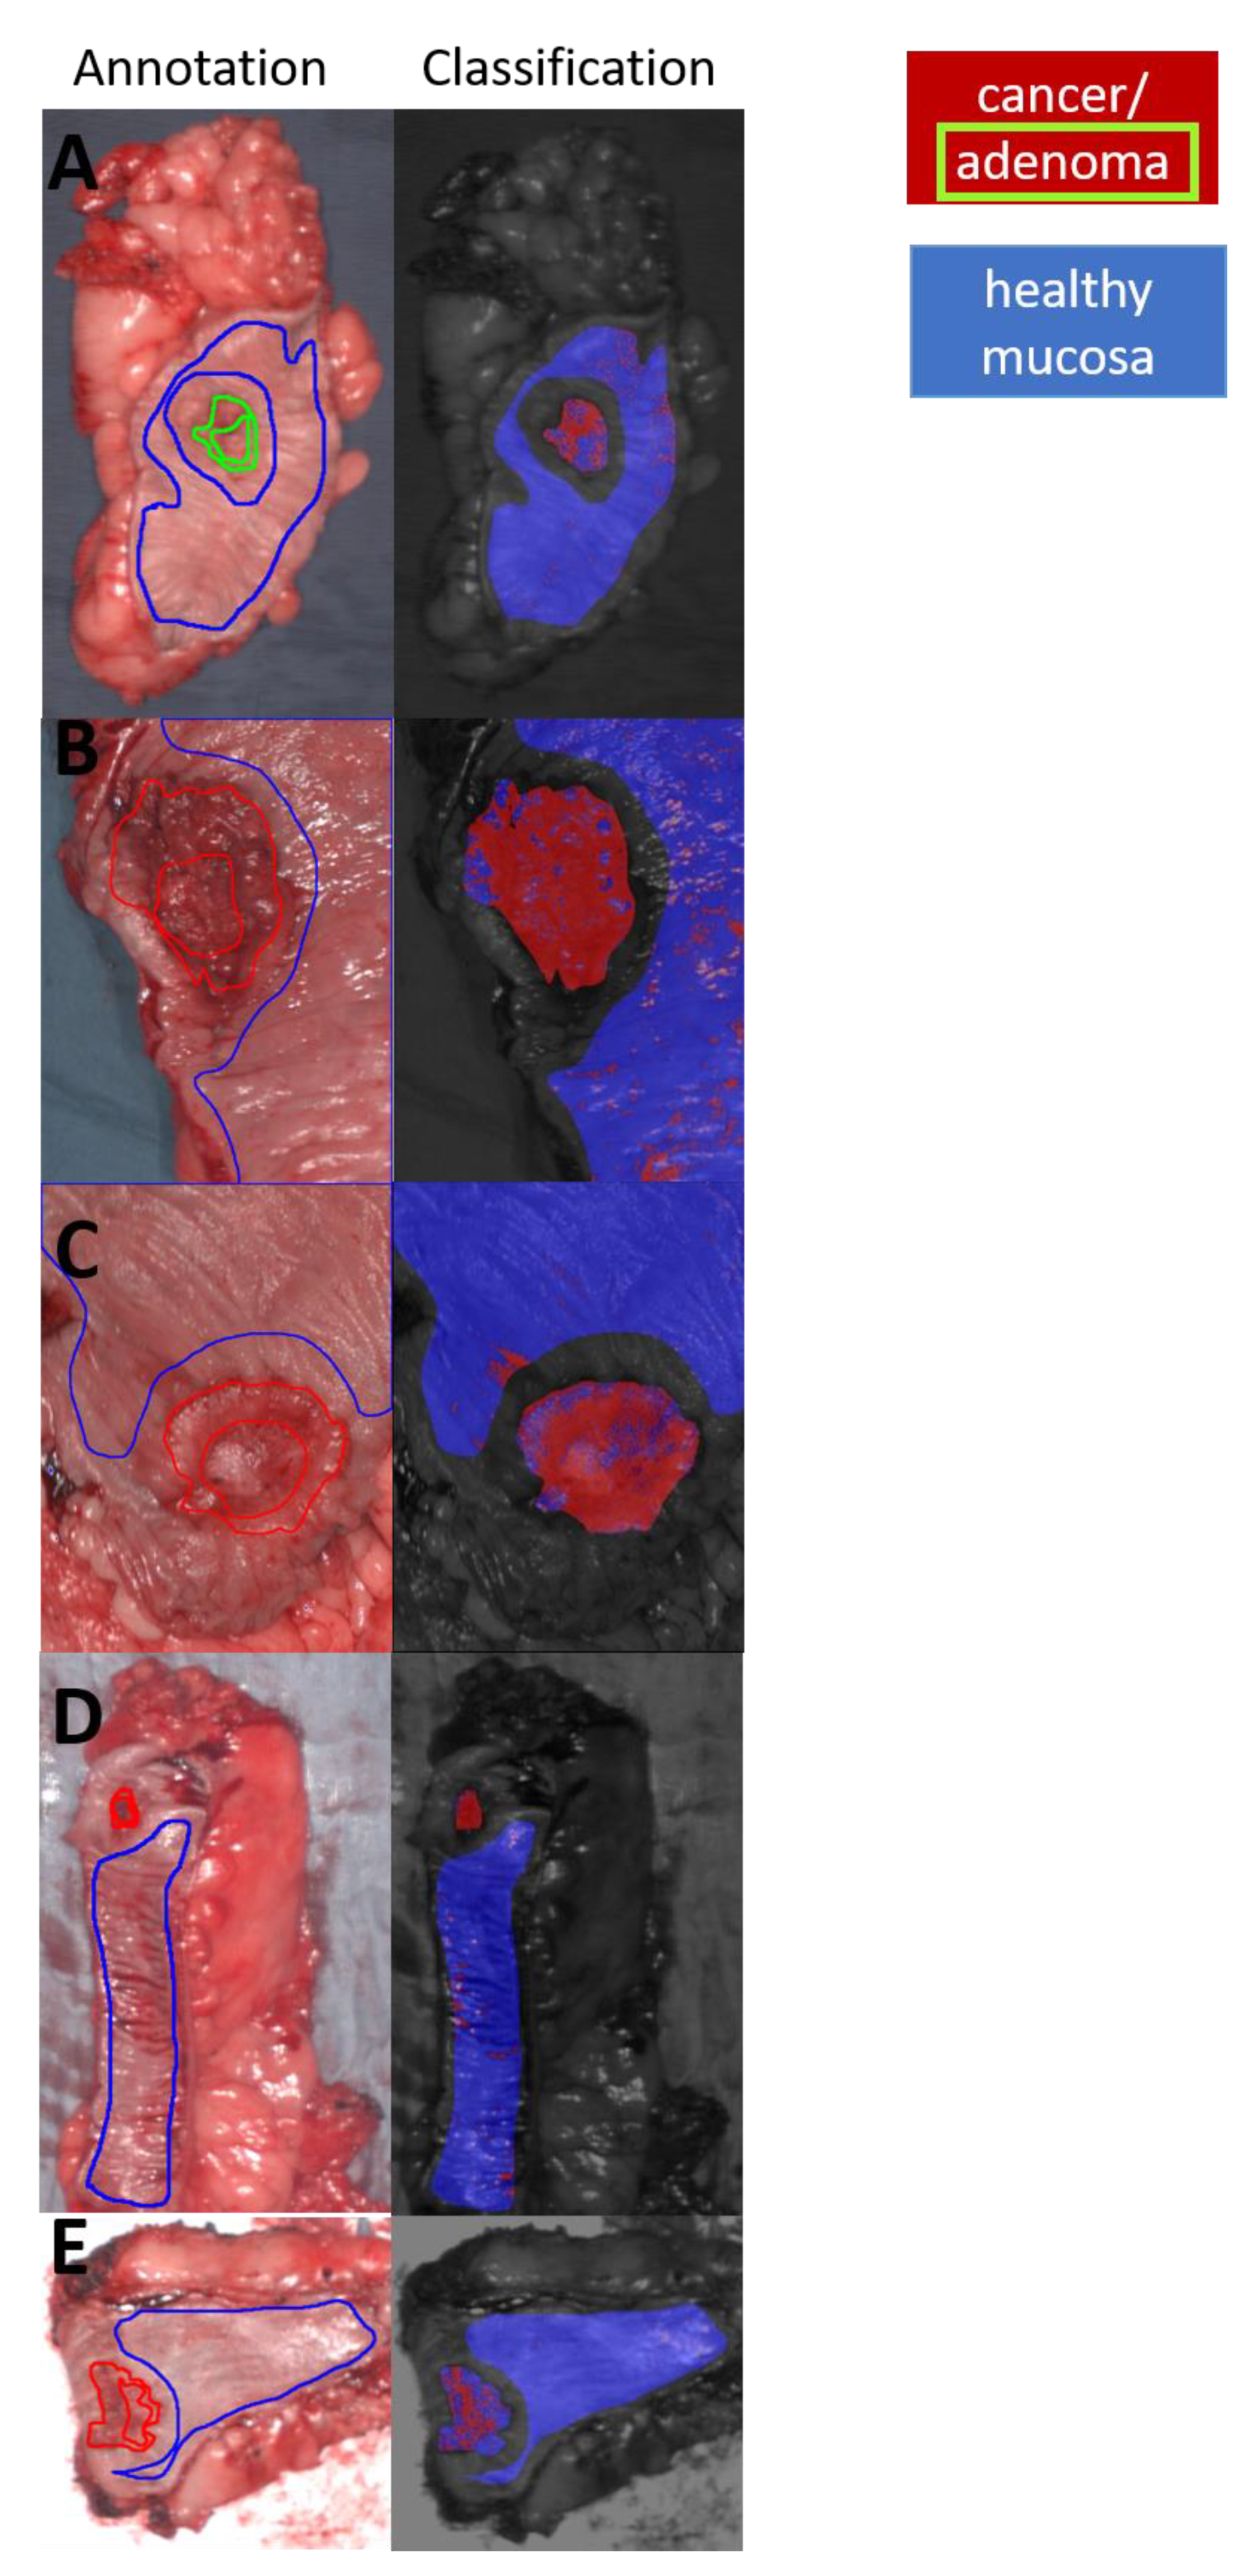

3.2. Classification and Visualization